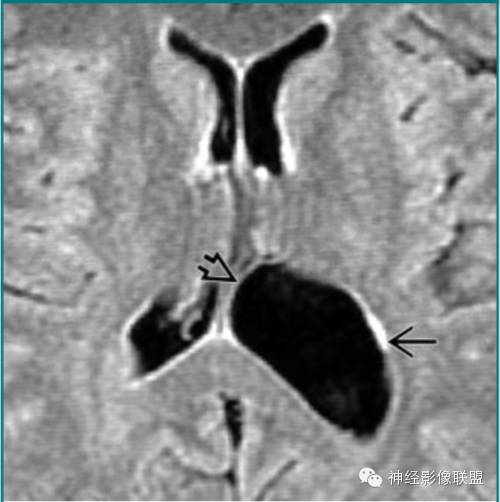

脑穿通畸形囊肿